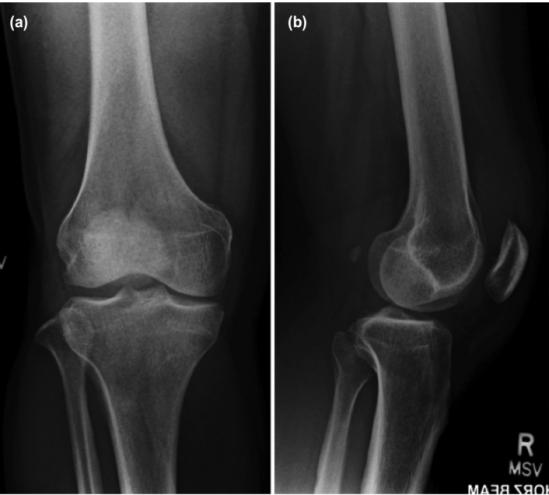

入院后,体格检查显示:右膝关节红肿,存在中度积液和内侧关节线轻度压痛。受疼痛限制,患者右膝活动范围为10°~40°。实验室检查:WBC水平增加(10.6×109/L)、ESR升高(8mm/hr)、CRP水平升高(60.5mg/L)、尿酸水平升高(575umol/L)。右膝X线检查显示退行性改变,并伴有内侧间室轻度狭窄(图1),关节内未见钙化。

图1 右膝正位(a)和侧位(b)检查未显示软骨钙沉积

在同一关节处同时发生痛风和假性痛风在临床十分罕见。急性痛风或假性痛风发作的患者通常存在炎症表现,例如关节渗出、疼痛以及关节活动受限等。通过肉眼观察关节抽吸液不能有效进行鉴别。抽吸液浑浊反映了细胞数量的增加,在痛风或假性痛风中均可出现。痛风合并假性痛风的诊断需要借助X线和偏振光显微镜检查。本例患者证实不存在软骨钙沉着并不能排除并发假性痛风的可能。